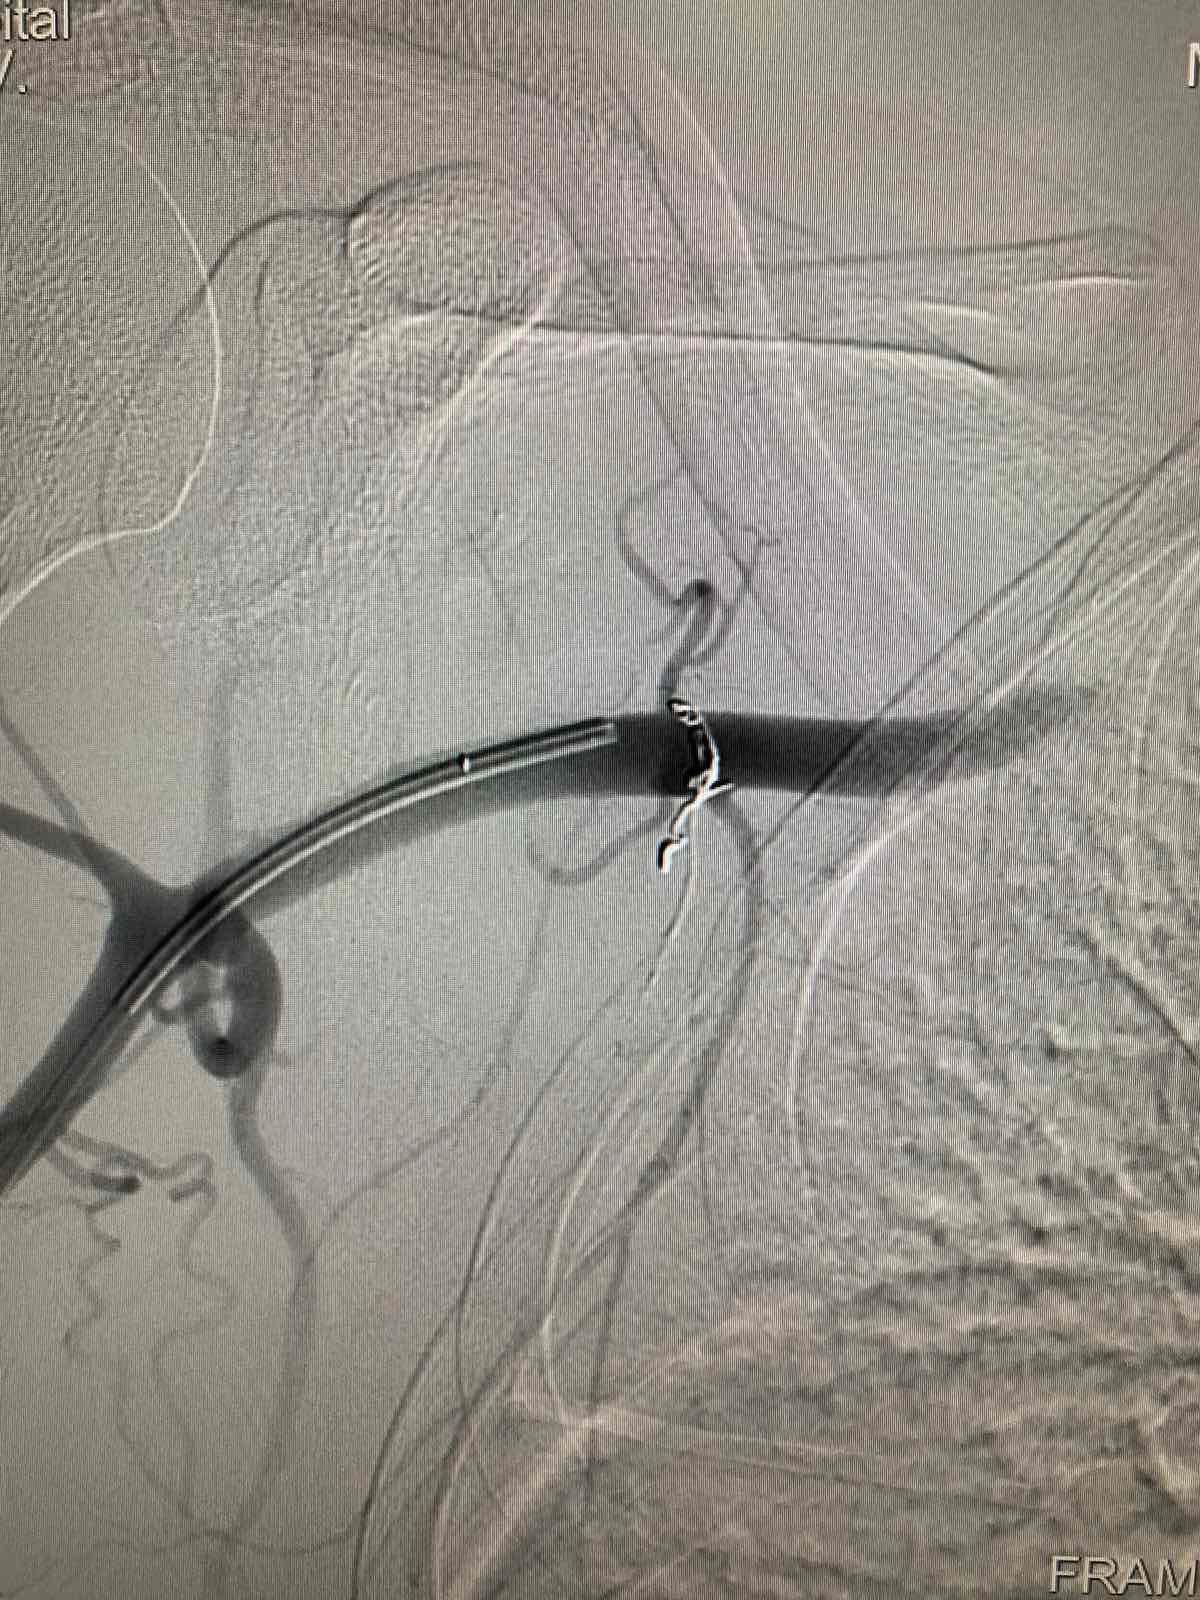

Мигом собралась хирургическая бригада и сделали ангиографию. Оказалось, что был крошечный, практически незаметный рентгену, фрагмент оболочки от извлеченной ранее пули. Этот кусок металла повредил одну из ветвей подключичной артерии.

Медики говорят, что из-за разрыва стенки образовалась ложная аневризма. Врачи еще называют "бомбой замедленного действия". Все потому, что аневризма может в любой момент вызвать несовместимое с жизнью артериальное кровотечение.

Хирурги провели чрезвычайно сложное вмешательство: исключили травматическую аневризму микроспиралями и "заклеили" поврежденные стенки артерии.